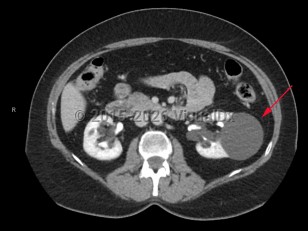

Simple renal cysts are common renal lesions (70%); the majority are benign, and further imaging is not required.

The presentation of renal cysts varies based on the cause, and physical examination may reveal a palpable flank or abdominal mass. Radiographic findings of a thick irregular wall, thick septations, or multilocular findings are concerning for malignancy.